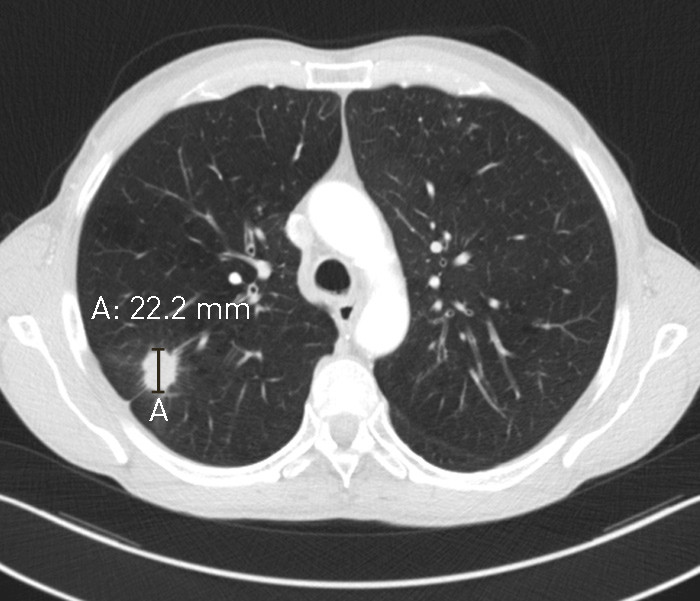

Hos pasienten disse bildene er fra, var svulsten klart synlig og greit tilgjengelig for behandling med stereotaktisk stråleterapi ved første undersøkelse (fig 1). Av ulike grunner gikk det 2,5 måneder før vedkommende kom til behandling og planlegging av stråleterapi med dedikert CT ble gjort (fig 2). Svulsten var da fordoblet i diameter og var størrelsesmessig på grensen for kurerende stråleterapi.

Bildene understreker viktigheten av et raskt utredningsløp og at det motsatte kan influere på pasientens sjanse for kurerende behandling.